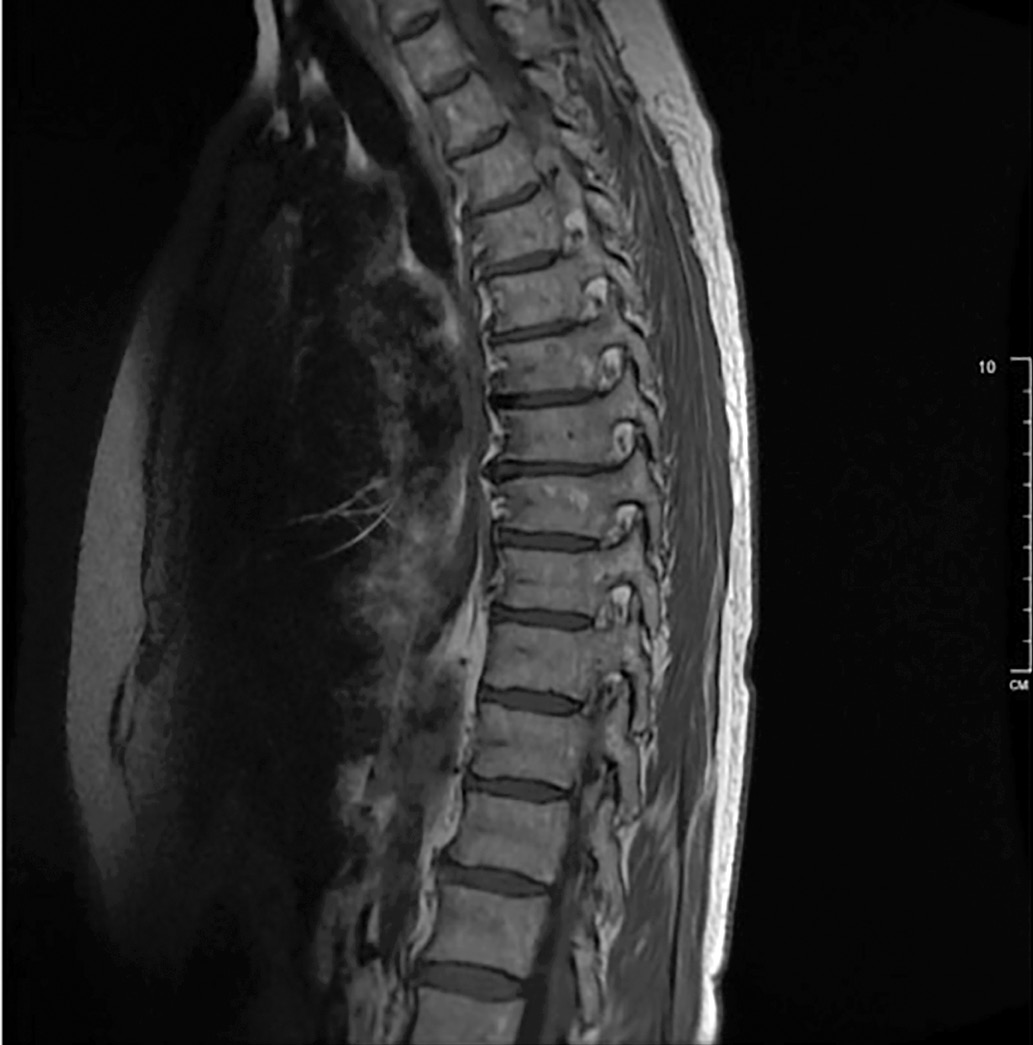

При исследовании состояния костной ткани маркеры костного обмена — в пределах референсных значений: остеокальцин — 25,31 нг/мл (24,0–70,0), С-концевой телопептид коллагена 1 типа — 0,65 нг/мл (0,10–0,85). По данным МРТ грудного и поясничного отделов позвоночника (рис. 2, 3) — картина дегенеративно-дистрофических изменений (остеохондроз, спондилоартроз), грыжа межпозвонкового диска на уровне Th5-6 и Th8-9, выстояние межпозвонкового диска на уровне Th7-8, Th11-12, Th12/L1 и L4/L5, гемангиома в теле Th8 позвонка, протрузия межпозвонкового диска на уровне L4/L5. Данных за наличие компрессионных переломов позвонков не выявлено. По данным рентген-денситометрии выявлено снижение МПКТ в L1–L4 до -2.5 SD по Т-критерию — соответствует остеопорозу, в шейке левой бедренной кости — до -2.2 SD, в бедре в целом — до -1.9 SD, в лучевой кости — 1/3 до -2.0 SD по Т-критерию.

Рисунок 2. МРТ грудного отдела позвоночника.

Рисунок 3. МРТ поясничного отдела позвоночника.